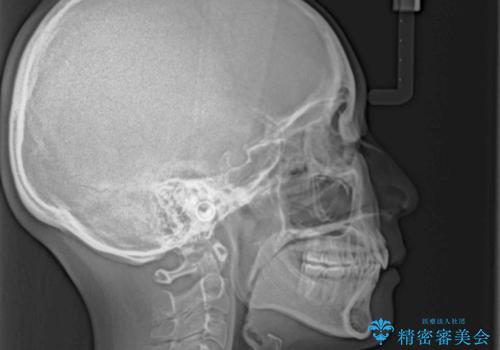

目立たない裏側装置 ハーフリンガルの抜歯矯正

- 口元の突出感を気にして来院された患者様です。

上下左右の第一小臼歯4本を抜歯して口元を下げる治療計画としました。

目立たない装置が希望であったため、上顎が裏側装置である、ハーフリンガル装置を選択されました。

3年半ほどで終わる予定でしたが、途中引っ越し、出産、引っ越し、出産を繰り返し、なかなか来院することができず、装置を外すまでに8年以上の期間がかかってしまいました。